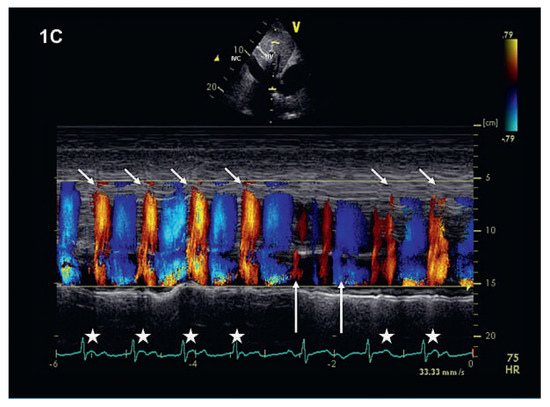

We report on the worldwide first implantation of a transcatheter valve in mitral position using a surgical approach to treat severe combined mitral valve disease, complicated by massive calcifications of the whole mitral anulus. The management of suc...